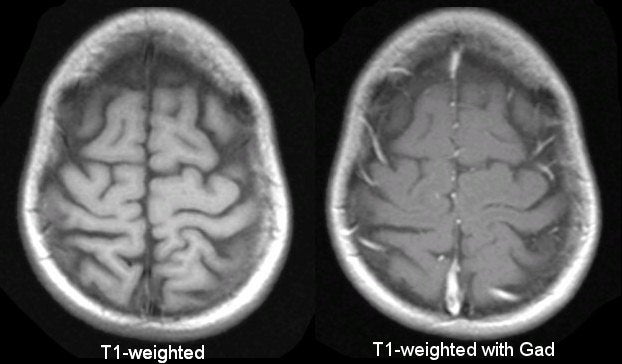

MRI Basics

https://case.edu/med/neurology/NR/T1 T1 gad.jpg

Gadolinium Contrast

https://www.radiologymasterclass.co.uk/images/mri/mri_gad.jpg?mtime=20210304211353&focal=none